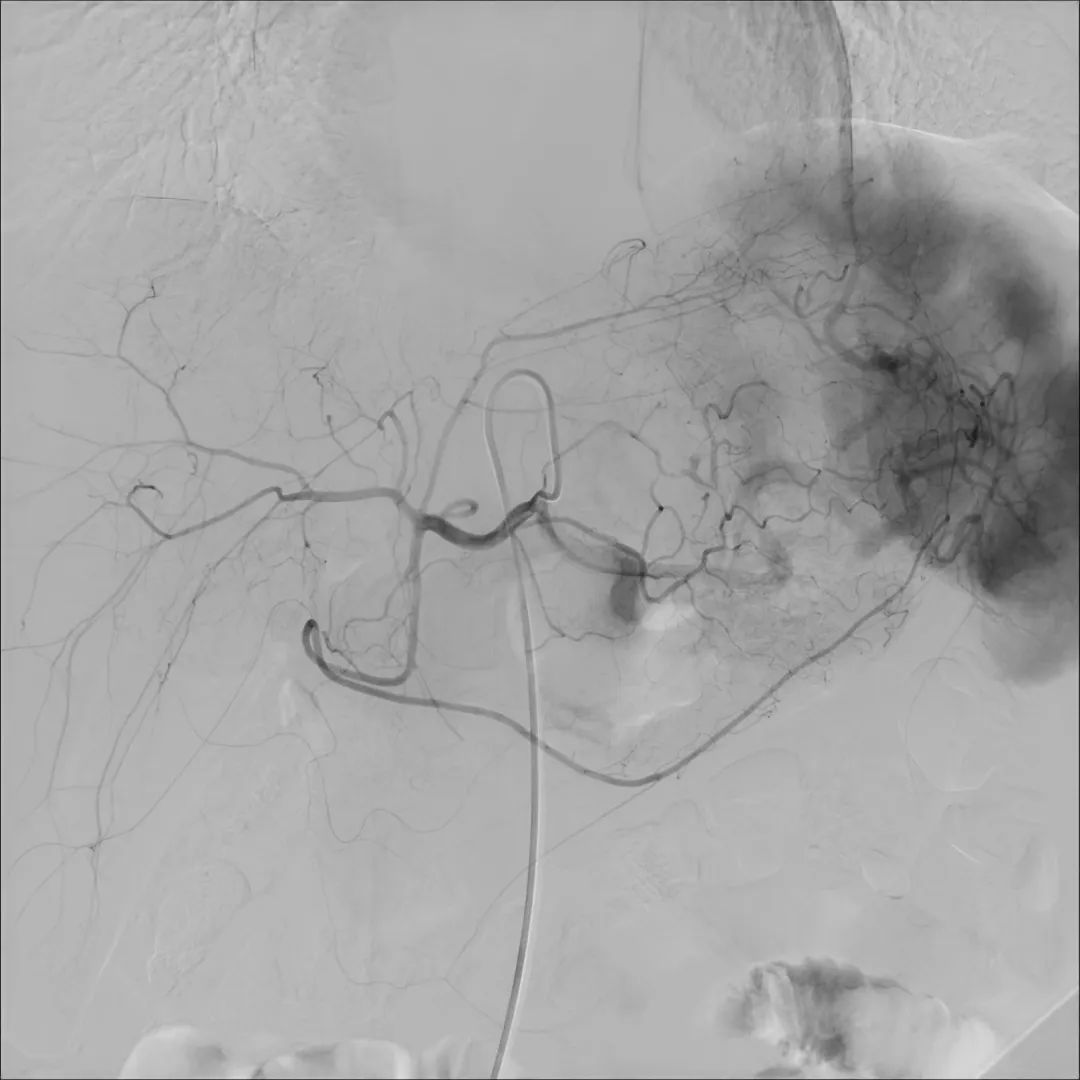

如何治療呢,可以使用血管造影X射線機(jī)(簡(jiǎn)稱(chēng):DSA),通過(guò)介入的方式治療,包括:

目前,唯邁醫(yī)療的DSA已裝機(jī)眾多三甲醫(yī)院,而剛剛完成裝機(jī)的濟(jì)南三院也在數(shù)日內(nèi)完成幾十例介入手術(shù),涵蓋經(jīng)介入造影治療,外周血管造影治療,心臟造影支架置入,滿足臨床多科室使用。

肝動(dòng)脈造影治療

神經(jīng)造影

心臟造影

支氣管動(dòng)脈造影治療

下腔靜脈+濾器